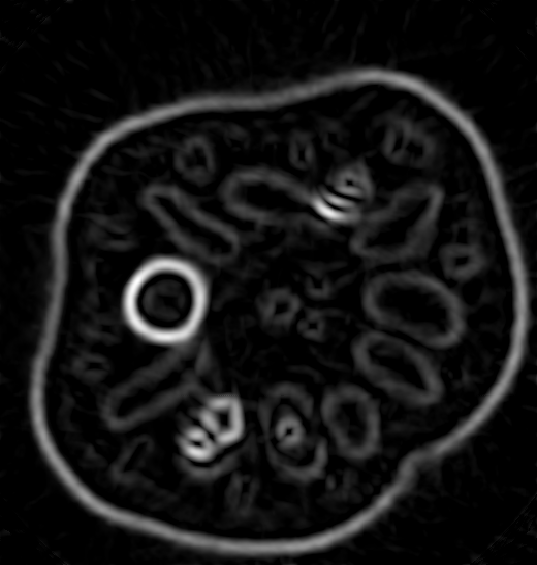

4.1 Reconstruction of the Laplacian feature map

We first investigate the feasibility of the proposed approach for recovering the Laplacian of the initial image. For our first experiment, we use a phantom image, which is defined as a characteristic function of the union of three discs and has the size N×N𝑁𝑁N\times N with N=200𝑁200N=200, cf. Figure 1(a). Since, according to the sampling condition (2.5), full aliasing free angular sampling requires πNs=472𝜋subscript𝑁𝑠472\lceil\pi N_{s}\rceil=472 samples in the s𝑠s-variable, we computed tomographic data at 2Ns+1=3012subscript𝑁𝑠13012N_{s}+1=301 equally spaced signed distances s[1.5,1.5]subscript𝑠1.51.5s_{\ell}\in[-1.5,1.5] and at Nφ=40subscript𝑁𝜑40N_{\varphi}=40 equally spaced directions in [0,π)0𝜋[0,\pi). This data is properly sampled in the s𝑠s-variable, but undersampled in the angular variable φ𝜑\varphi, cf. Figure 1(b).

From this data, we computed the approximate Laplacian reconstruction, shown in Figure 1(c), using the standard FBP algorithm in combination with the LoG-filtered data uLoGsyΘsubscript𝑠subscript𝑢LoGsubscript𝑦Θu_{\rm LoG}\circledast_{s}y_{\Theta} that we computed in a preprocessing step using the LoG data filter from Proposition 3.4. It can be clearly observed that FBP introduces prominent undersampling artefacts (streaks), so that many edges in the calculated feature map are not related to the actual image features. This shows, that the edge maps computed by FBP (from undersampled data) can include unreliable information and even falsify the true edge information (since artefacts and actual edges superimpose). In a more realistic setup, this could be even worse, since artefacts may not be that clearly distinguishable from actual edges.

Refer to caption

(a) Phantom

(b) CT data

(c) FBP-LoG reconstruction

Figure 4.1: Reconstruction of the Laplacian feature map using FBP. The phantom image of size 200×200200200200\times 200 consisting of a union of three discs (1(a)) and the corresponding angularly undersampled CT data, measured at 40 equispaced angles in [0,π)0𝜋[0,\pi) and properly sampled in the s𝑠s-variable with 301301301 equispaced samples s[1.5,1.5]subscript𝑠1.51.5s_{\ell}\in[-1.5,1.5] (1(b)). Subfigure (1(c)) shows the Laplacian of Gaussian (LoG) reconstruction using the standard FBP algorithm. It can be clearly observed that FBP introduces prominent streaking artefacts that are due to the angular undersampling.